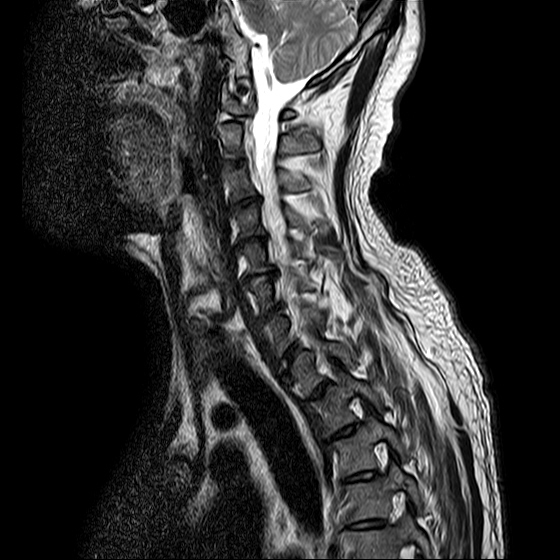

ũ Ͻ е鲲 ǰ ϴ. ڸ 4°Դϴ. ũ ϴ. (ڸǥغ ǥغ ) @ : 2014. 2.15 ĺ Ȳġ Ͽ. -> κ ǿ ġϿ պ ϱ. @ 2014. 3. 27 к mri, ct ũ ϰ ؾ Ѵٰ. @ ũ ġ ͳ Ͽ ڸǥغ Ͽ. ϱ : .(ó ) 2014. 4. 12() --- <1°> : Ͽ ȸ . 㳻 : (ڱ , Ӹ е ħ ˷. ¿ . ų ɰų Ҷ ̰ų ڼ . 201.4. 4. 13() ---<2°> 1. ħ Ͼ ¿ ȭ . 2. ħ е ħ . 3. ü ƮĪ ˷. ڼ ˷ֽŴ ϸ ڼ ùٸ ϸ Ÿ ˷ֽ Ư ƮĪ ϸ Ѱ پ 2014. 4. 14() ---<3°> : : پ(ó ߴ.) 㳻 : 1. ħ Ͼ ¿ ȭ . 2. ũ ˷ . 2014. 4. 14() ---<4°> : پ(ó .) 㳻 : 1. 繫ǿ ũ ٽ 2. ũ ˷ ϸ ڼ ϸ ȸ ̷ ɴ 2~3 ϸ ȸȴٰ Ͻô ū 븦 Ͽ ȸϵ ϰڽϴ. ȸ Ź帳ϴ. ũ mri Ȳ Դϴ. Ű 179 86 51 ()ijħ ڸǥغ ǥغ ˰Ե ͳ ˻ڷ õ ()ijħ ڸǥغ ǥغ ϱ ȣϽ 6C.ڸ 6C.ھ Ḳ 7C.Ȳġ 1T.Ȳġ 1T. κ ()ũ( ߰Ż) ڸ(߹) ũ(߰) Ը ũ(߰Ż)ġ, ()ijħ ڸǥغ ǥغ ϰ ߴ ġ 1. : 2014. 2.15 2. ġ : Ʒ(ô߿ ) , ȱ 3. **뺴 : ˾. Ƽ (ũ ) 4. ó : ڰ, 3 Ⱓ mypol()ó. ȭ. 3 5. ü ġ . |